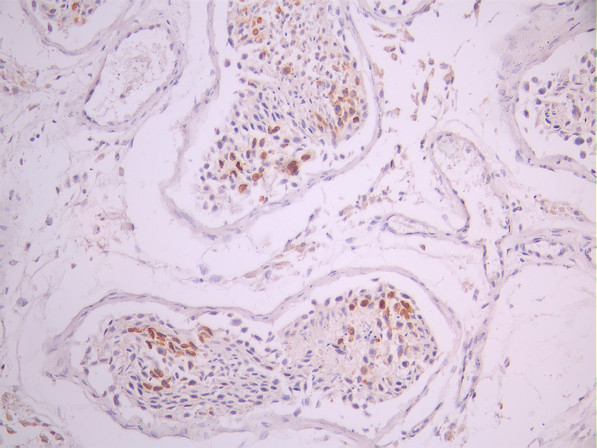

• IHC image of CSB-RA112927A0HU diluted at 1:100 and staining in paraffin-embedded human testis tissue performed on a Leica BondTM system. After dewaxing and hydration, antigen retrieval was mediated by high pressure in a citrate buffer (pH 6.0). Section was blocked with 10% normal goat serum 30min at RT. Then primary antibody (1% BSA) was incubated at 4°C overnight. The primary is detected by a Goat anti-rabbit polymer IgG labeled by HRP and visualized using 0.05% DAB.

IHC 1:50-1:200